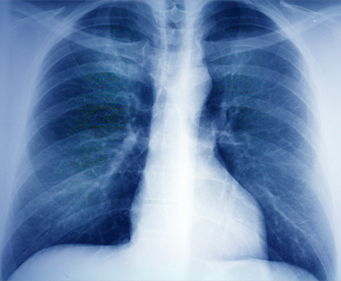

폐기능 검사

기능 검사는 개인의 호흡능력과 폐의 기본 기능이 얼마나 적절하게 이루어지는 지를 측정하는 검사로서 환자가 호소하는 증상(호흡곤란 등), 호흡기 질환의 중등도의 평가 및 치료방향의 설정과 치료의 효과판정에 큰 도움을 줄 수 있습니다.